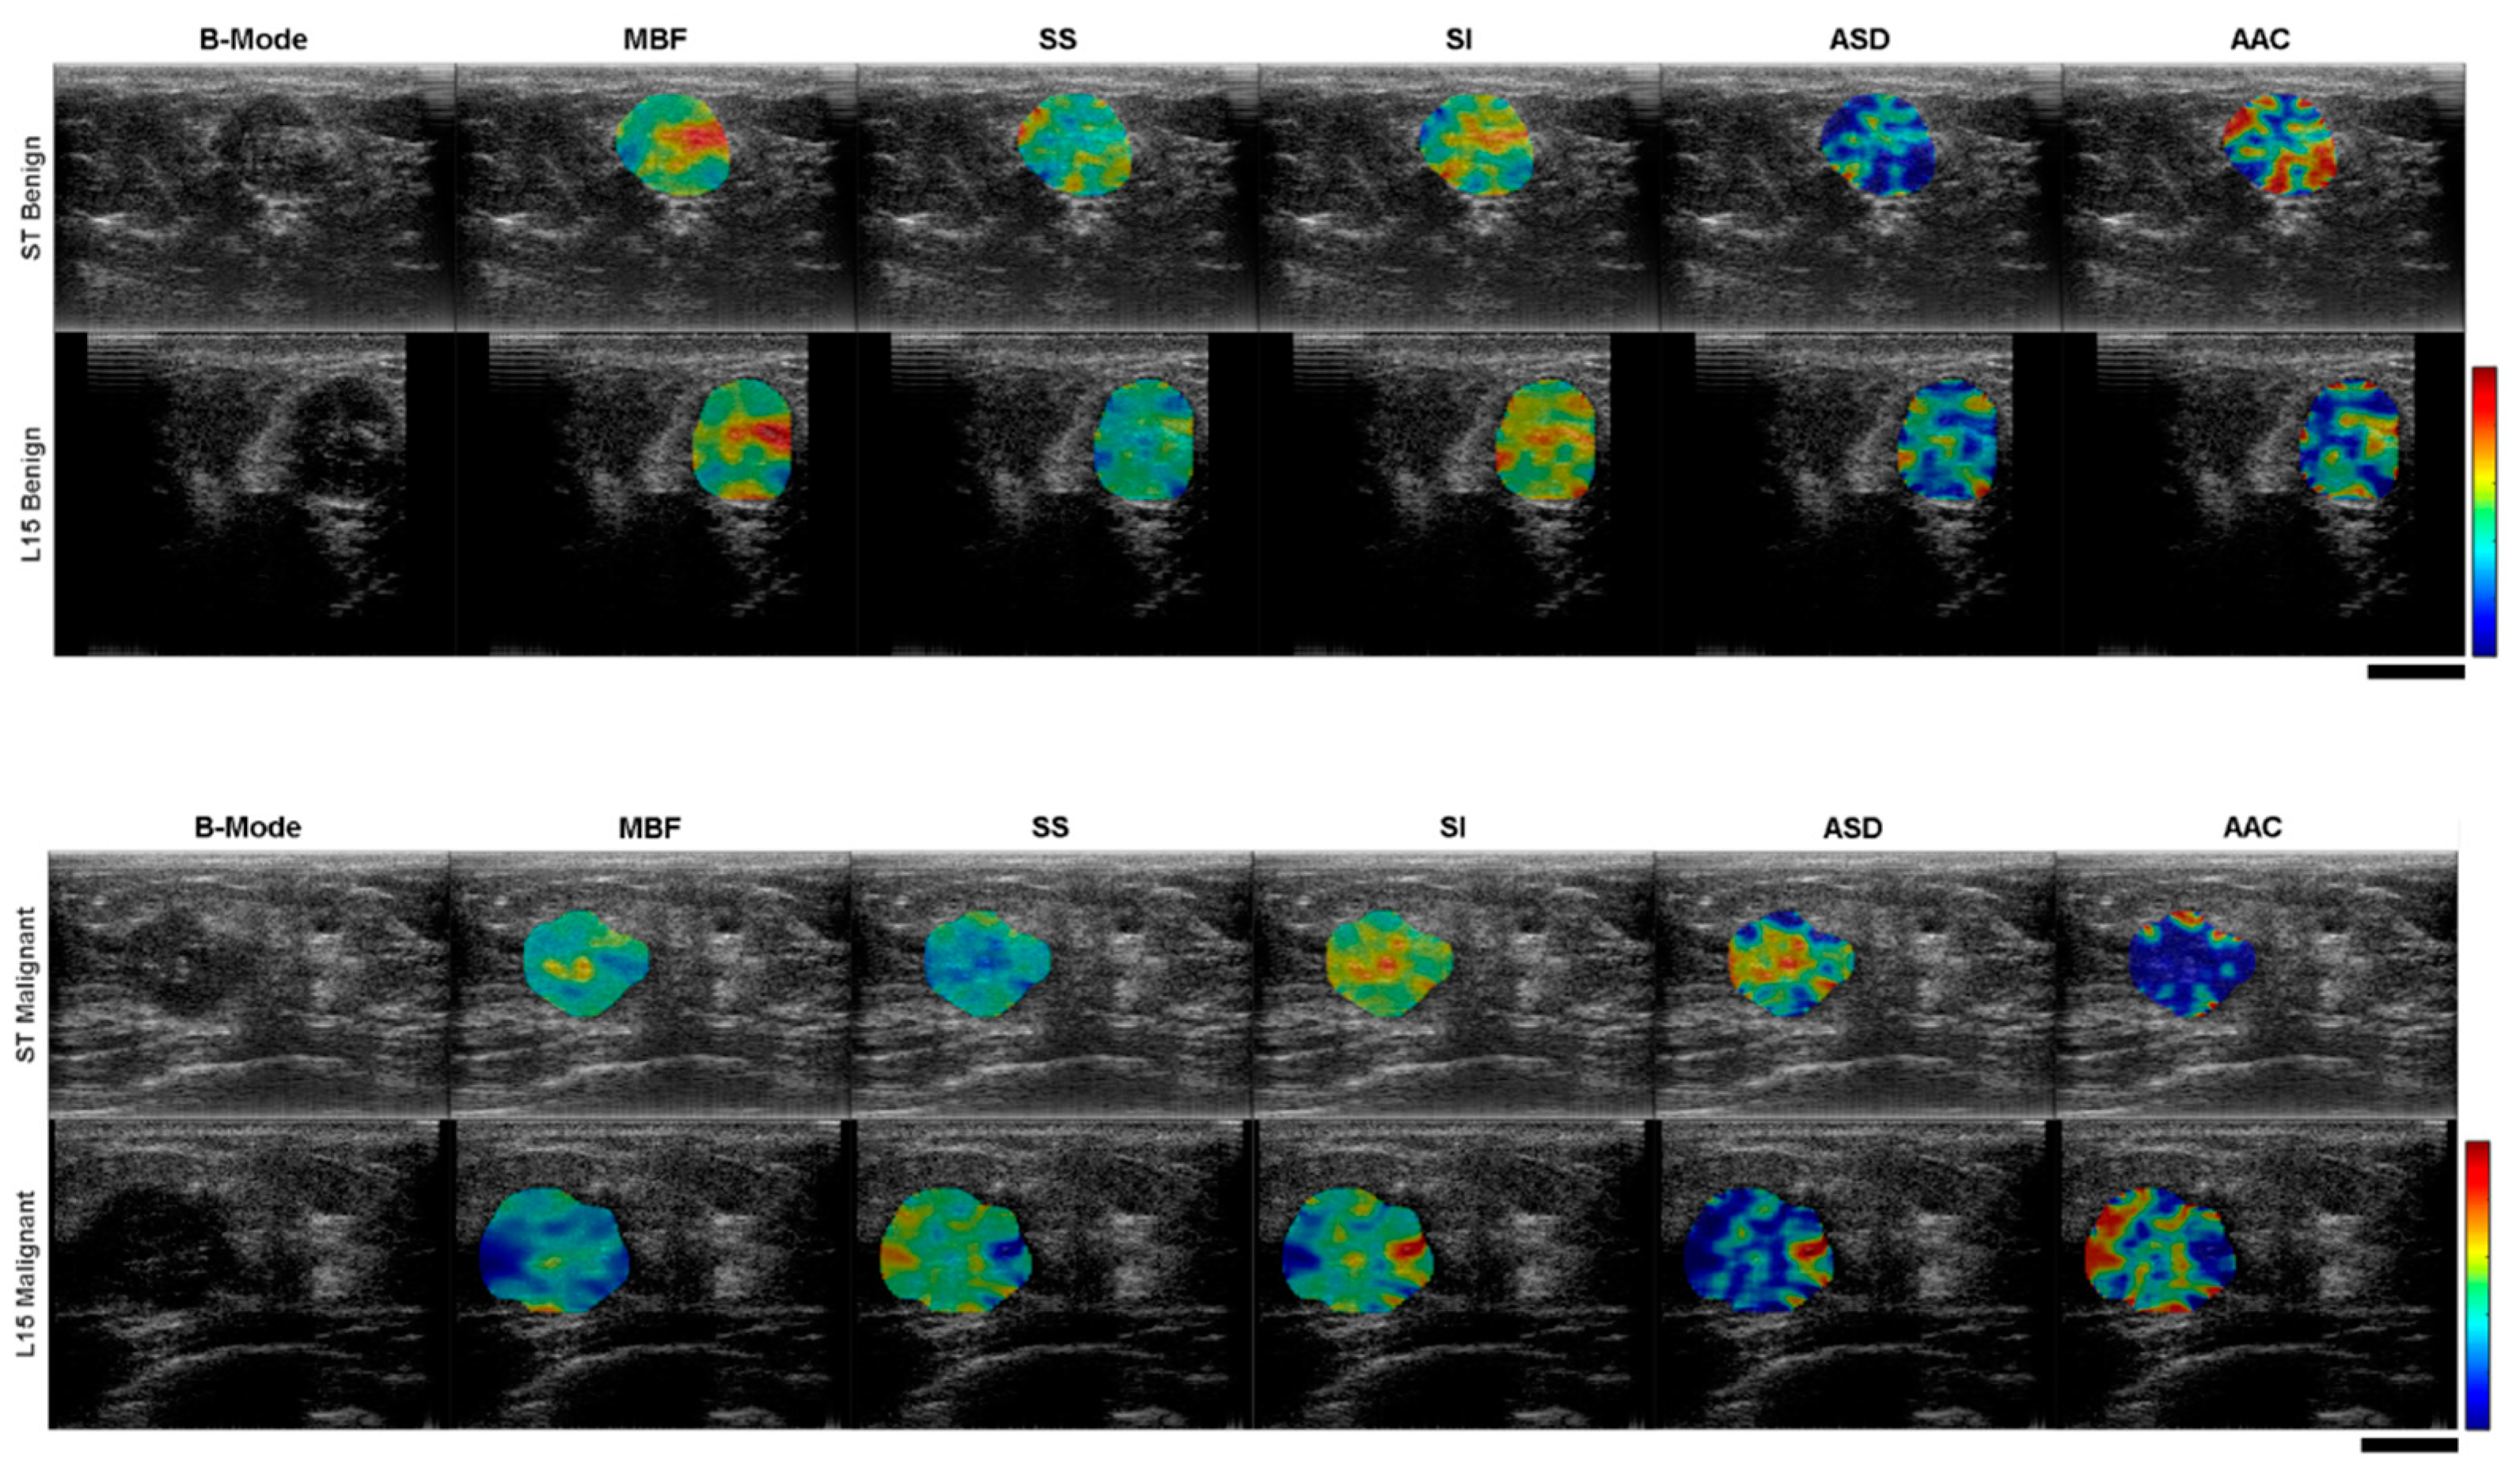

2.2. Ultrasound Data Analysis